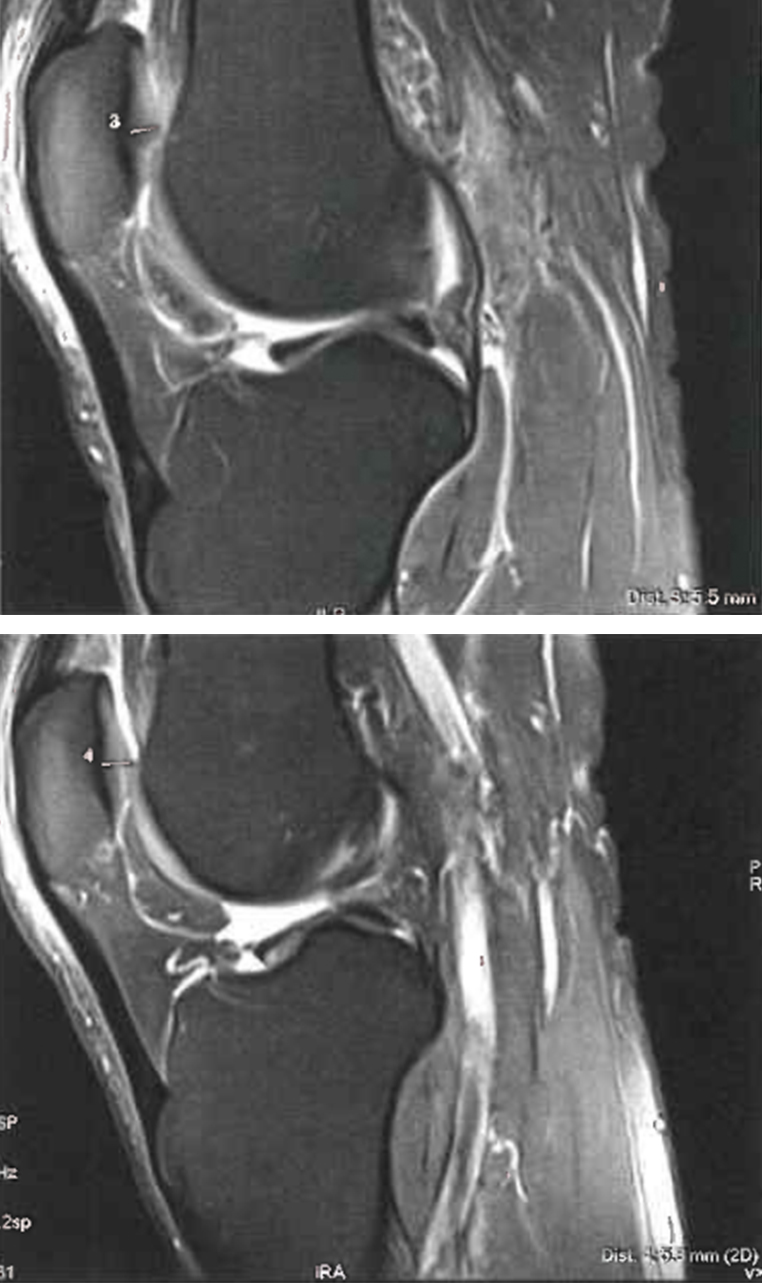

Uno studio osservazionale sperimentale, condotto dal Dipartimento di Scienze e Biotecnologie Medico-Chirurgiche della Sapienza Università di Roma – Polo Pontino, ha documentato gli effetti della terapia elettromagnetica a radiofrequenza non-termica nel trattamento dell’artrosi del ginocchio.